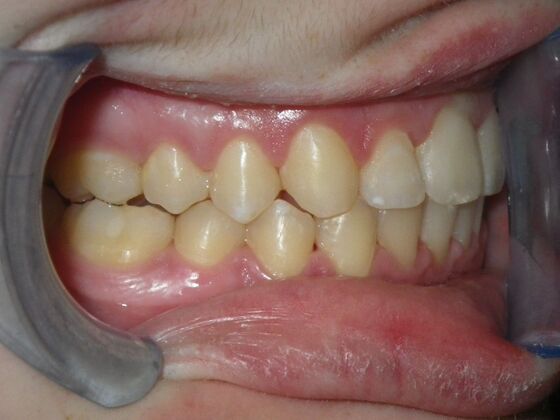

Orthodontics: Case 4

Description

Patient presents with constricted upper and lower arches, numerous crossbites on right side, with upright central incisors on upper arch that will need to be flaired to provide adequate lip support. I decided to use on this case self ligating brackets, to help with expansion purposes. This case turned out very well with flairing of upper centrals, crossbite corrections, expansion of arches, as well as establishing better arch form and symmetry.